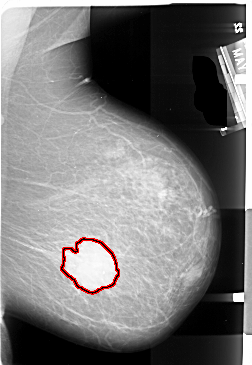

A_1004_1.RIGHT_MLO

FILE: A_1004_1.RIGHT_MLO.OVERLAY

TOTAL_ABNORMALITIES 1

ABNORMALITY 1

LESION_TYPE MASS SHAPE IRREGULAR MARGINS ILL_DEFINED

ASSESSMENT 5

SUBTLETY 5

PATHOLOGY MALIGNANT

TOTAL_OUTLINES 1

BOUNDARY